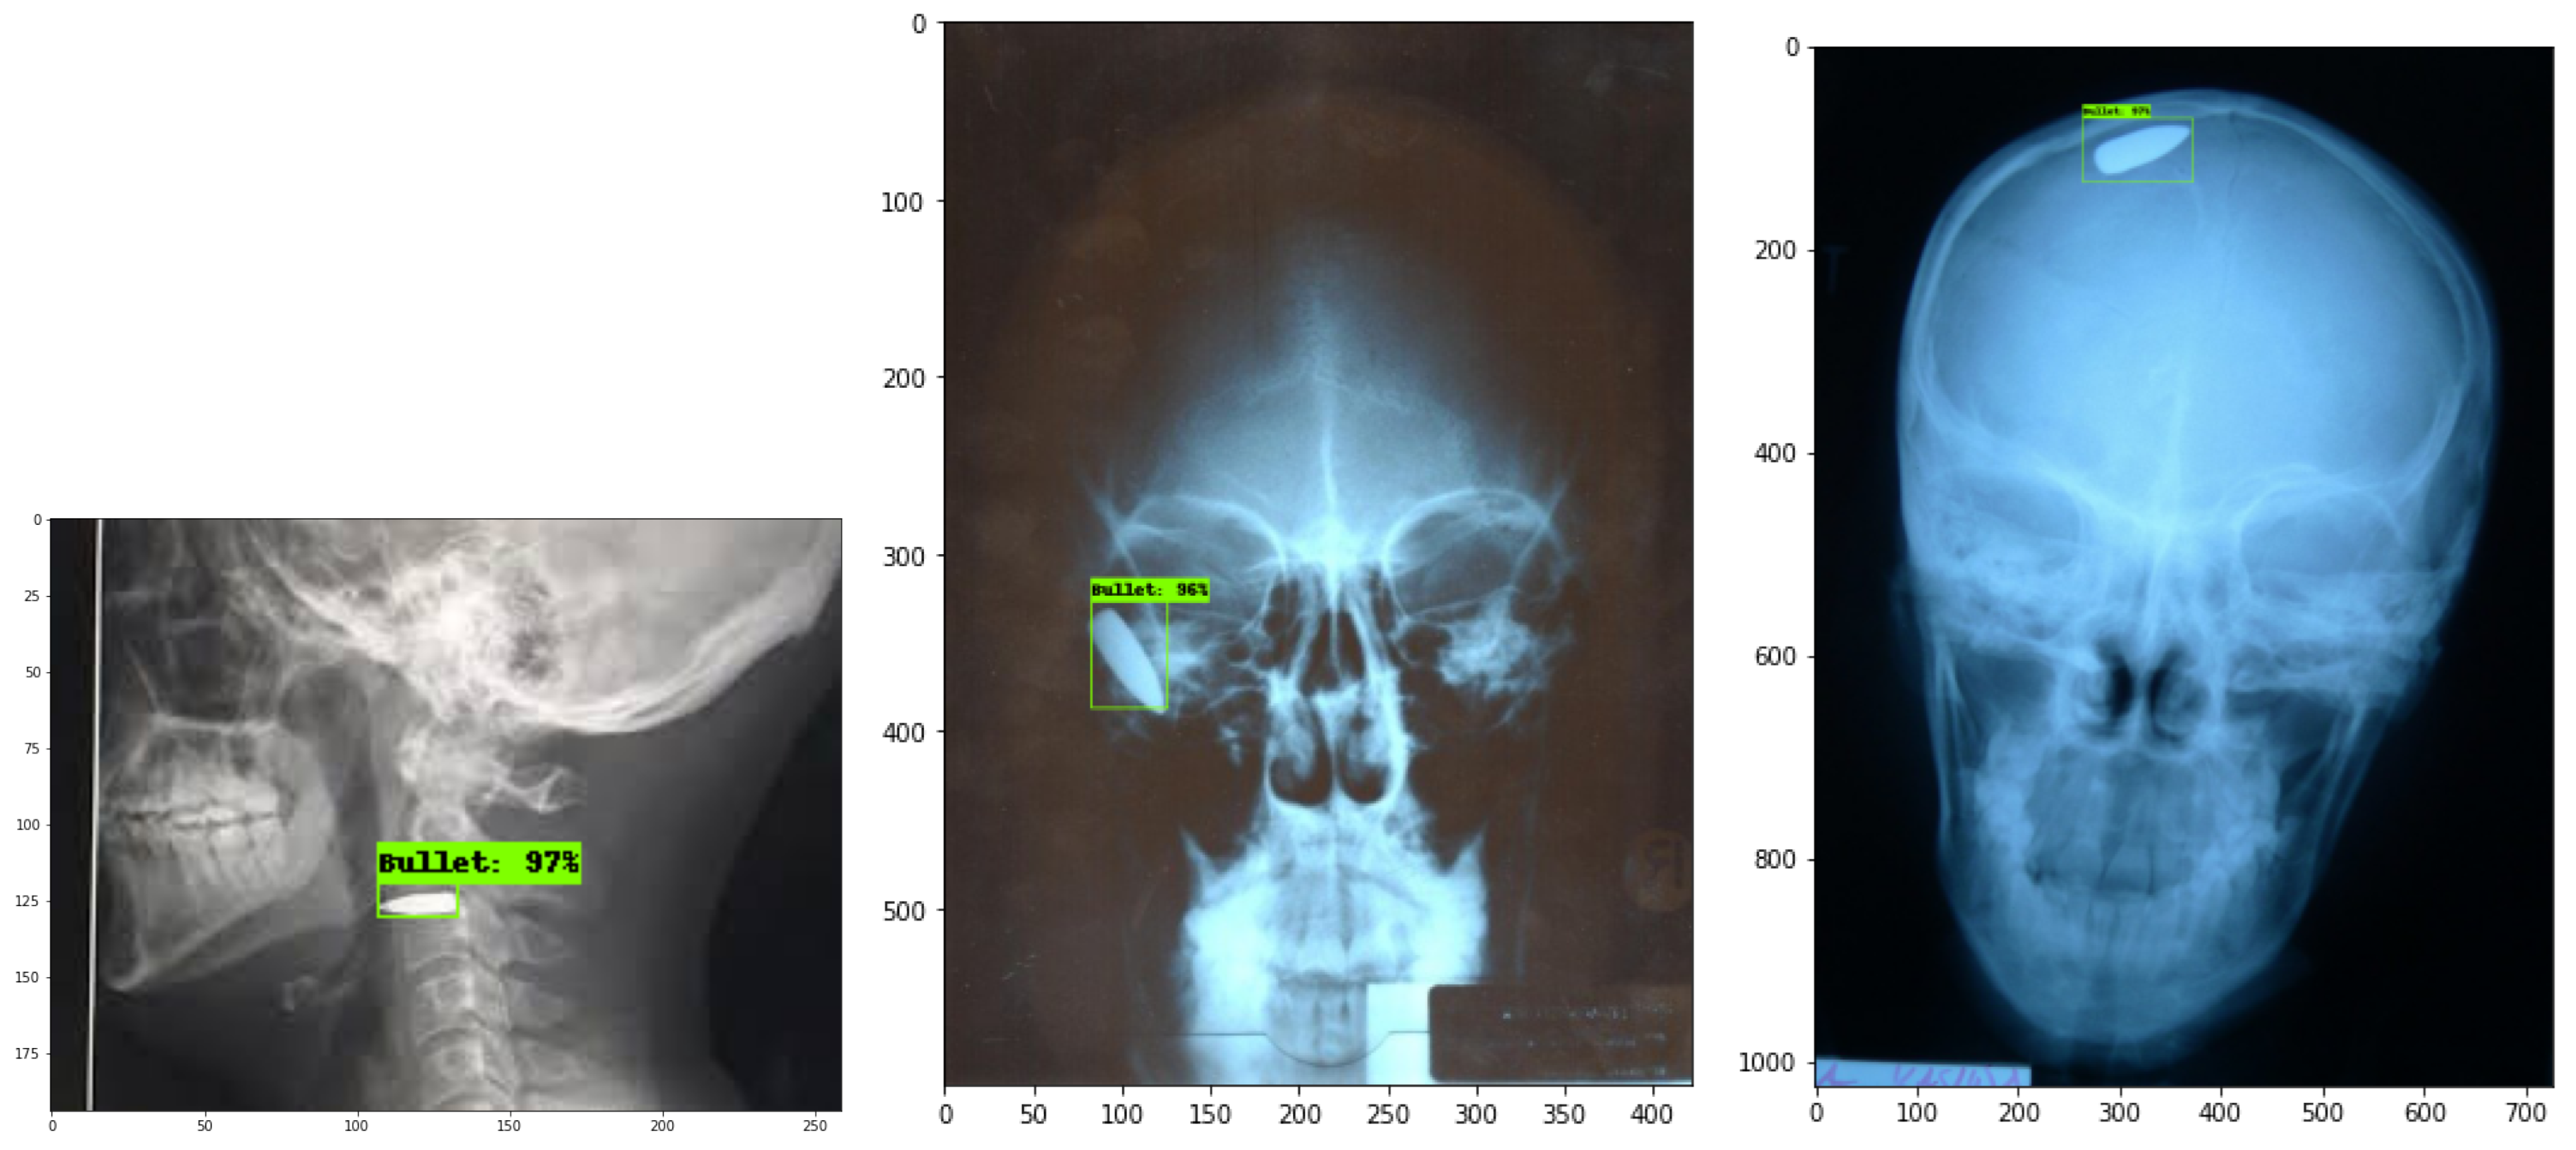

The evaluation included the testing of each model throughout chest X-ray examinations and gunshot wound (GSW) radiographs of the head, neck, leg, and abdomen region, according to Figure 6, Figure 7 and Figure 8. It is important to highlight that all results are based on actual radiographs rather than synthetic or augmented data. Performance improvements can be achieved by fine-tuning hyperparameters and increasing the number of training steps per model. For evaluation, we used the Intersection over Union (IoU) metric, setting a threshold value of 50. The model will produce a bounding box only when the predicted shape overlaps with the ground truth shape by at least 50% within their boundaries.

Figure 7. Neck and Head X-ray predictions.